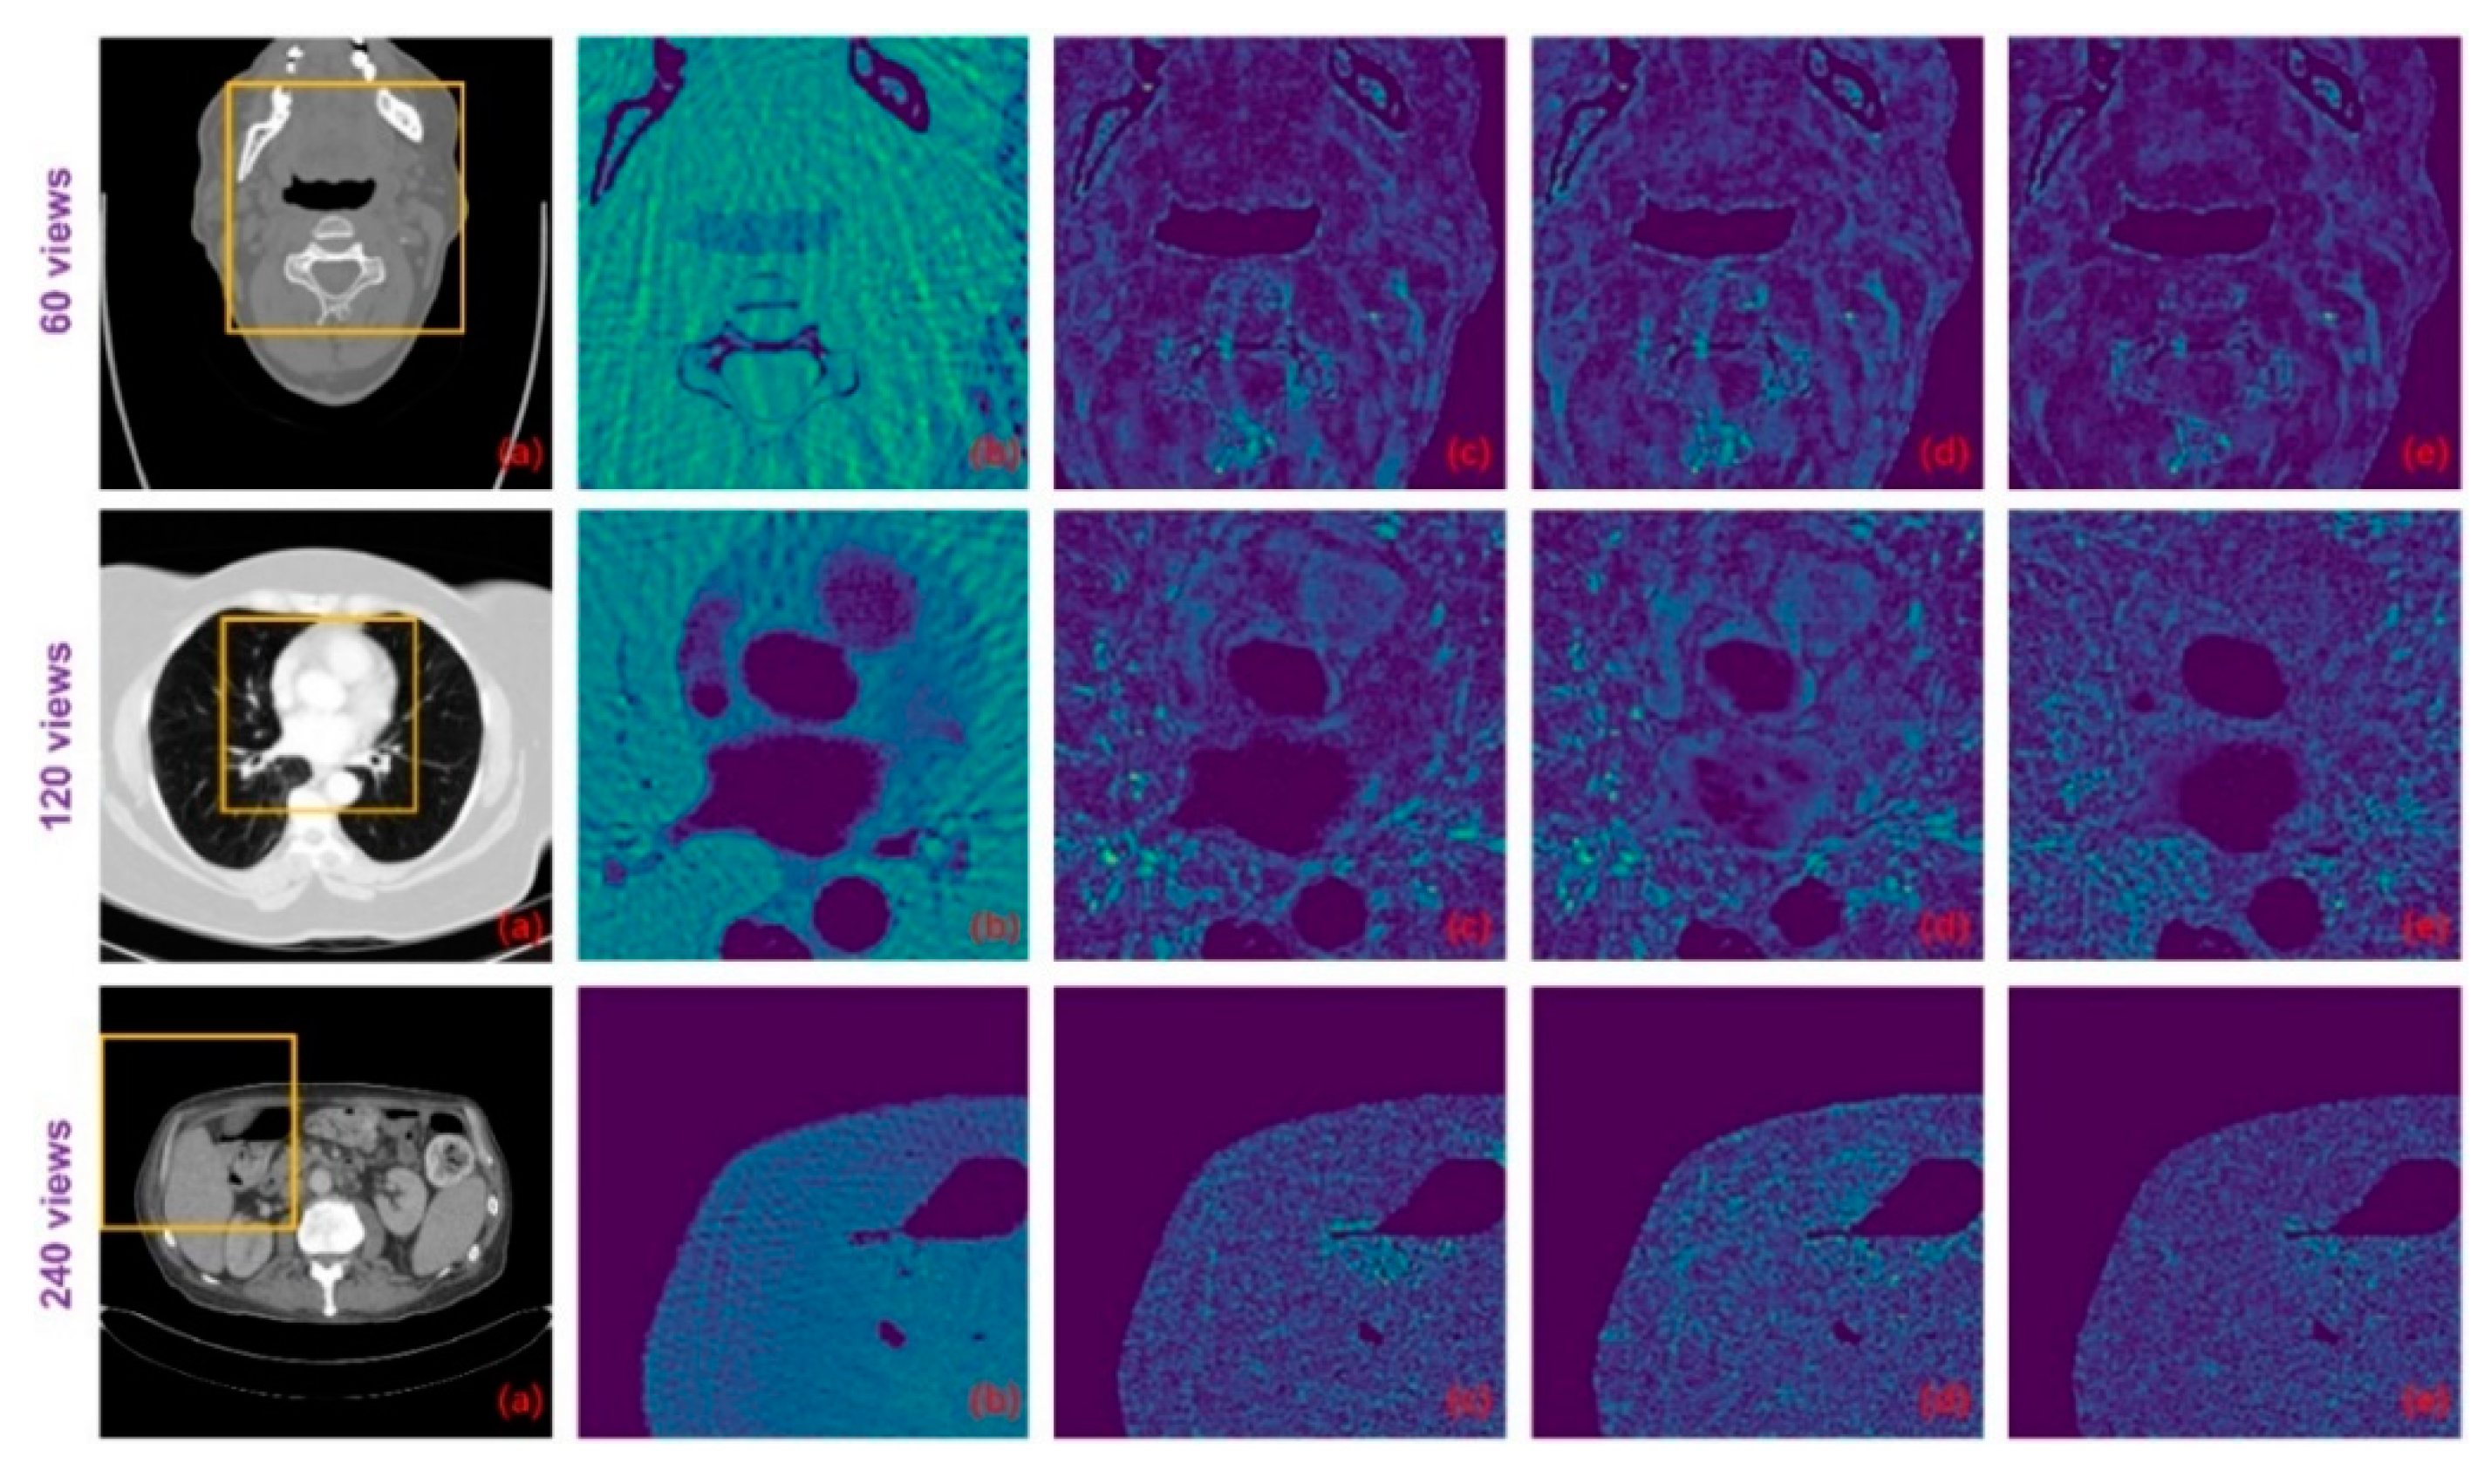

Figure 9.

The difference images between the ground-truth CT images and the images resulting from different methods: (a) ground truth; (b) FBP; (c) DD-Net; (d) DD-Net+; and (e) ours.

For the networks that contain three sets of parameters corresponding to different degradation levels, Improved GoogLeNet+ has a PSNR advantage over Improved GoogLeNet on 60 views and 120 views while SSIM has an advantage only on 60 views. The performance of Tight Frame U-NET+ is generally weaker than that of Tight Frame U-NET, which may be due to the fact that the training dataset of Tight Frame U-NET+ only targets one degradation level, while the training set of Tight Frame U-NET contains three types of degradation, which moderates the overfitting problem to some extent. The average performance of Red-CNN+ and DD-NET+ is better than that of Red-CNN and DD-NET, but still worse than that of our model and more parameters are used. The standard deviations of PSNR and SSIM for our method on the test dataset are shown in Table 3. Suppose the PSNR and SSIM results are both independent samples from a normally distributed population, Table 3 also displays the 95% confidence intervals for PSNR and SSIM results on the test dataset. Figure 9 displays the difference images between the result images and the ideal CT images. It can be seen that the proposed method can reduce the overall intensity error compared to other methods, therefore, achieves better visual performance.

With the explicit learning of degradation levels in both the frequency and image domain, our method outperforms all the deep learning-based methods in terms of different degradation levels and body parts, as well as achieves a satisfactory trade-off between the size of the network and the performance (Table 1). Moreover, the statistical significance of the testing results (Table 4 and Figure 10) demonstrates that the differences in the PSNR and SSIM results between the proposed method and other methods are statistically significant. In addition, our method achieves better visual results with more textual structure details and less reconstruction error (Figure 8 and Figure 9).